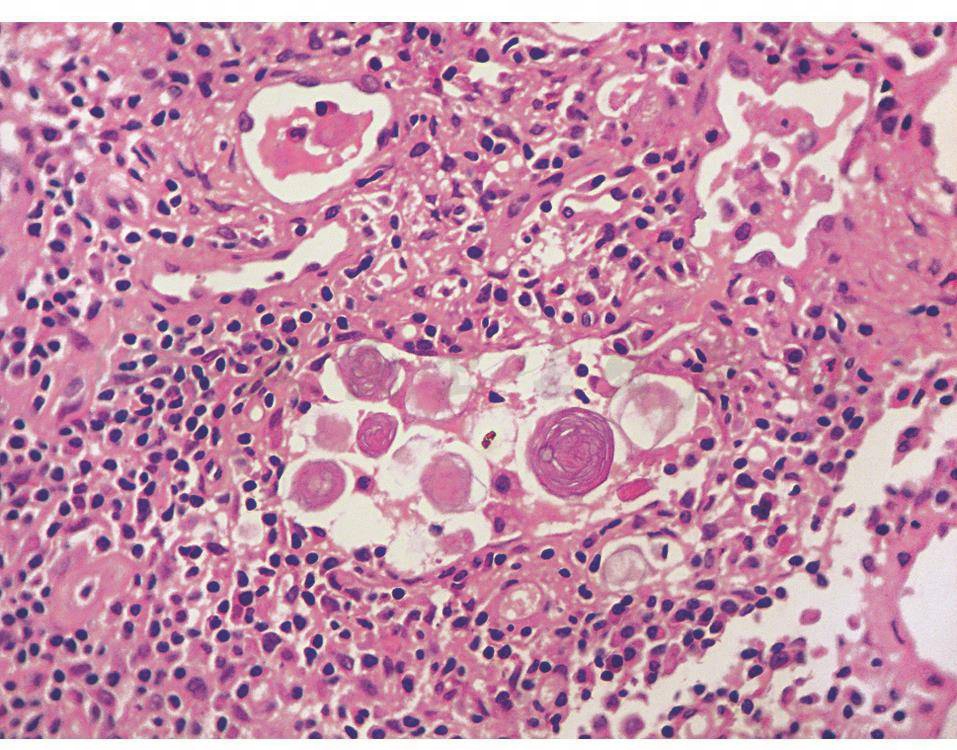

本病主要侵犯两肺,病肺变硬,重量明显增加,触之有沙砾感,切面呈“细纱纸”状纹理,主要分布于中下肺。镜下70%~80%的肺泡内有特征性的层状、年轮状、同心圆状微结石形成(似洋葱头皮),直径50~1000μm,微结石沿支气管、血管特别是叶间胸膜下分布偏多,几乎都位于肺泡腔内,但也可位于肺泡壁,向肺泡腔内凸入(图1)。微结石以钙、磷酸盐为主要成分,过碘酸希夫染色呈紫红色。肺泡灌洗液可见沙砾样物质沉积,沉渣包埋可见层状钙化小体。病变早期肺泡壁结构完整,进展期和末期伴有肺泡壁肥厚、间质纤维化等,可伴肺气肿和肺大疱。

图1肺泡微结石症的病理表现(HE×400)

肺泡间隔明显增宽,中等量淋巴细胞及浆细胞浸润,肺泡腔内可见多个同心层状结构的微结石。